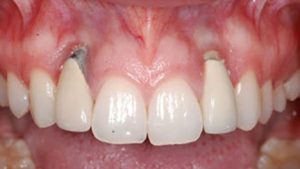

تحلیل لثه

اگر بافت لثه اطراف ایمپلنت شروع به تحلیل رفتن کند، می تواند پایه فلزی ایمپلنت را نمایان کند. این اغلب در نتیجه عفونت یا قرارگیری نامناسب ایمپلنت ها رخ می دهد.

پری ایمپلنتایتیس پیشرفته شامل گرانولاسیون های چرکی، تحلیل لثه و تحلیل استخوان اطراف ایمپلنت و دندان های مجاور است. موکوزیت و پری ایمپلنتایتیس توسط عوامل زیادی ایجاد می شوند که می توان آنها را به دو گروه تقسیم کرد: مواردی که ناشی از خطاهای پزشکی هستند و مواردی که ناشی از اقدامات نادرست بیمار می باشند.